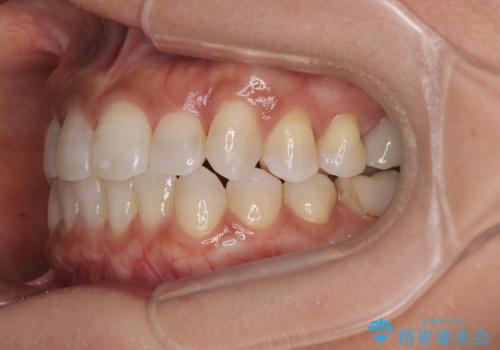

クロスバイトを治したい インビザラインによる矯正治療

- 前歯のクロスバイトを気にして来院された患者様です。

上下ともに、前歯部を中心にやや叢生が認められる程度であったため、ワイヤーでもインビザラインでも、どちらでも対応可能な状態でした。

咬合力が非常に強く、治療が進むにつれて上下奥歯が離開してくることが予想されるため、治療途中から上下の顎間ゴムを使用することを理解いただき、インビザラインによる矯正治療を行うこととしました。

咬合力による臼歯離開は顎間ゴムで改善されましたが、それとは別に下顎小臼歯がマウスピースに追従せず、補正のためのゴムかけが必要となりました。

大変なゴムかけ作業を頑張っていただき、無事に治療を終えることができました。